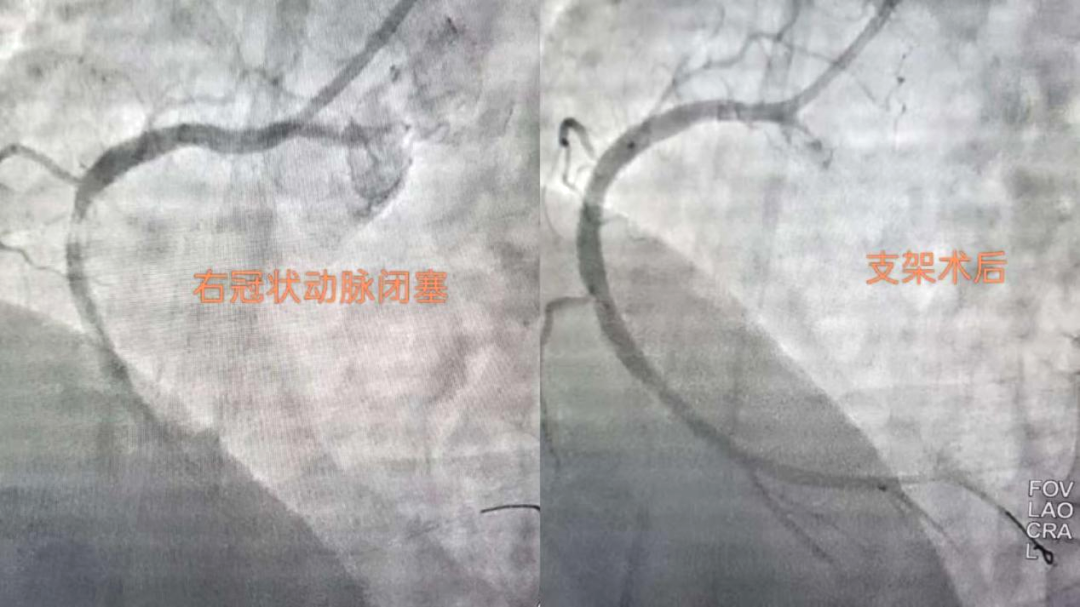

搶時(shí)間就是搶生命!06:46穿刺,06:47成功,06:49冠脈造影明確:右冠狀動脈中段完全閉塞。導(dǎo)絲迅速通過,支架精準(zhǔn)植入,07:03血流恢復(fù),手術(shù)成功結(jié)束。患者胸痛明顯緩解,生命體征趨于平穩(wěn)。從入院到血管再通,不到兩小時(shí)。